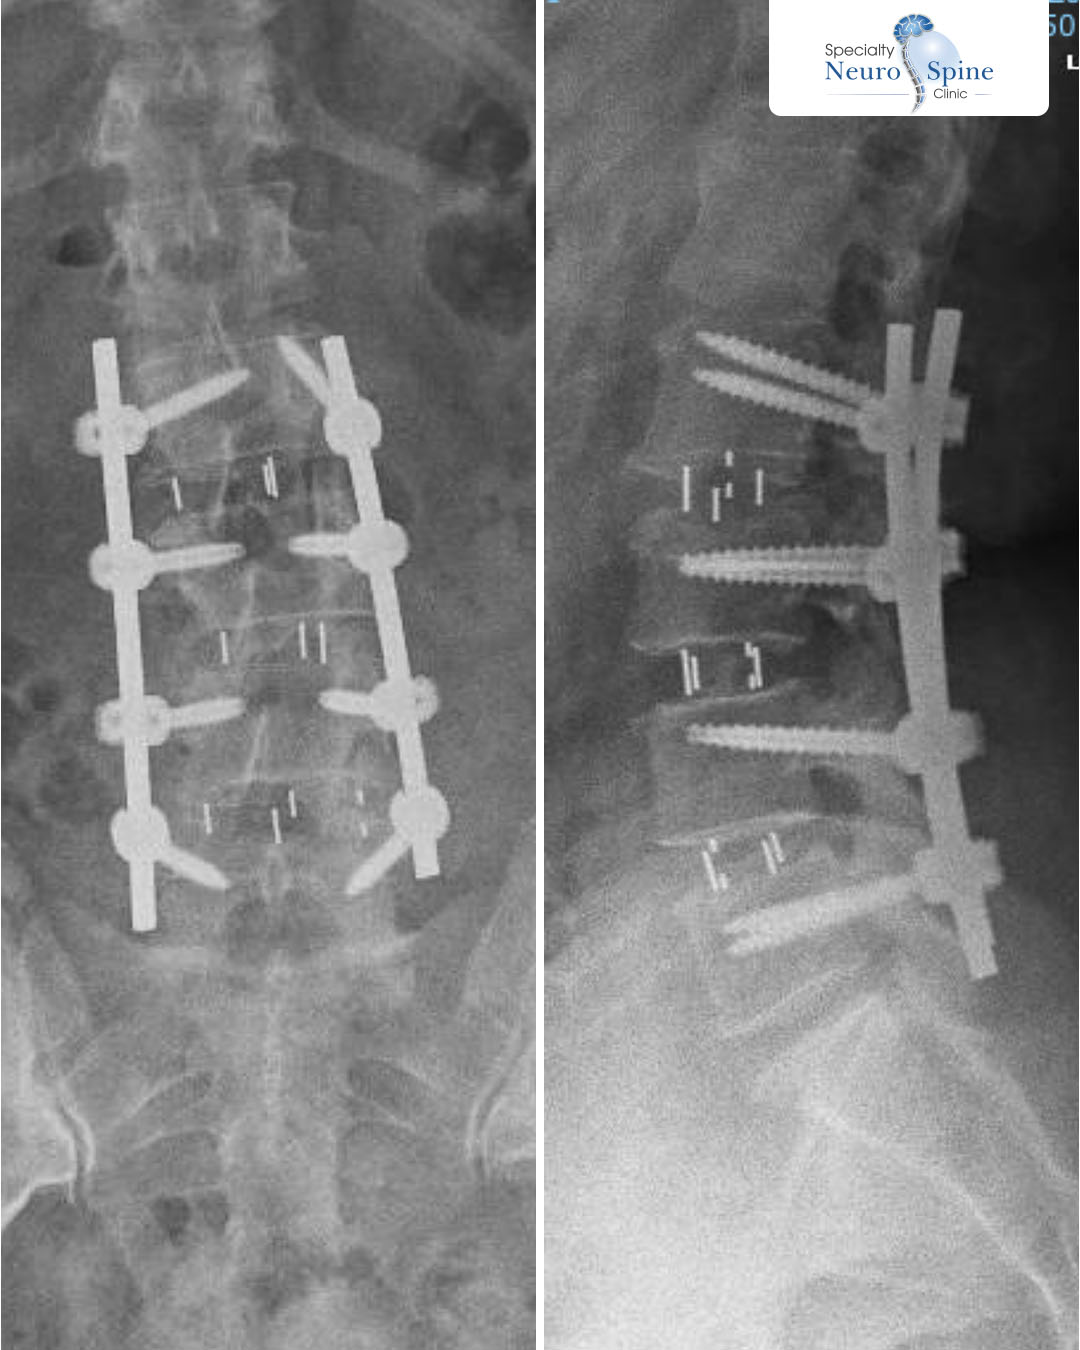

Anterior and lateral X-ray images of our dear patient Muntaha, a 56 years old from Iraq, who underwent lumbar spinal fusion surgery from the second to the fifth lumbar vertebra (L2–L5), performed by Dr. FirasHusban using minimally invasive endoscopic techniques.